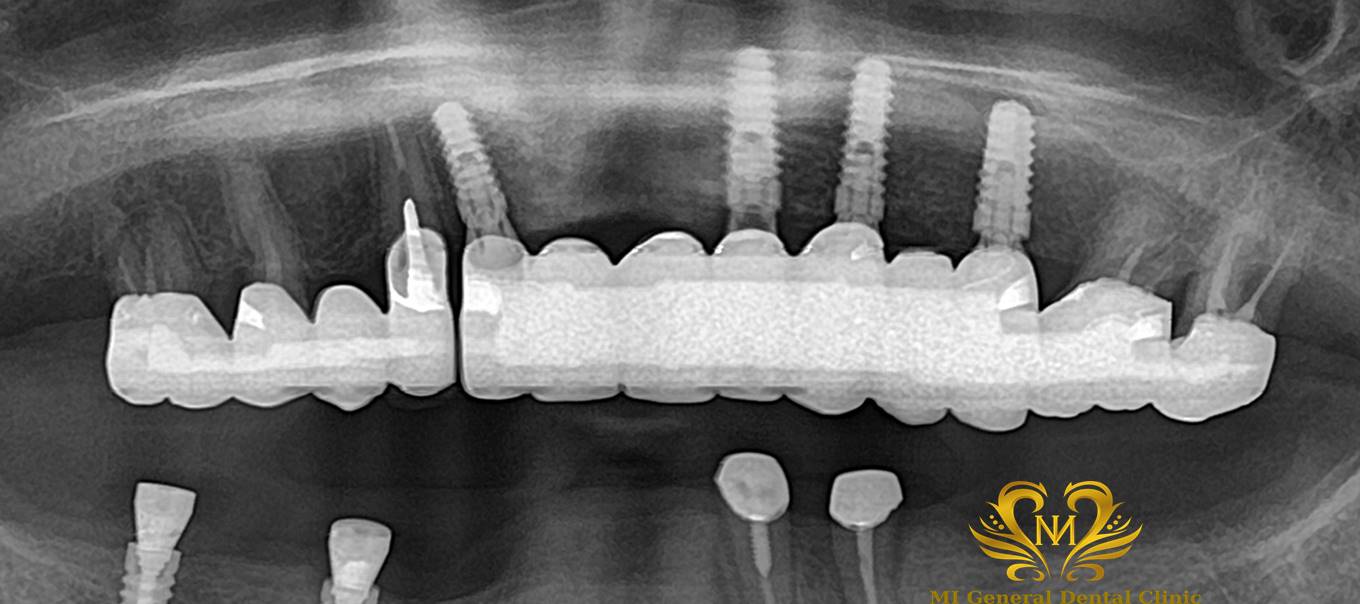

治療前

長年上顎に入れ歯を入れていて、上手く食事が出来なかった方です。

噛めない。見た目が悪い。入れ歯が違和感が大きい。

60代

女性

10ヶ月